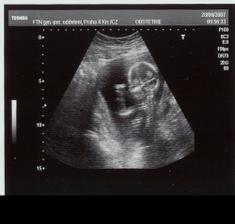

22.6.2007 první ultrazvuk -----

21.11.2007 jsme byly na 3D,4D UTZ mame cca 1296g a malá vůbec nespolupracovala proste spala ----- 4.1.2008 tak mame cca 2001g ----- 18.1.2008 kontrola dopadla dobře otvirame se jak máme ----- 25.1.2008 další kontrola -----tak kontrola se nekonala misto ni se narodila mala v 37+6tt v 6:17 vážila 2520g a měřila 46cm ____________________________________________________________________________________________________________________________________________________